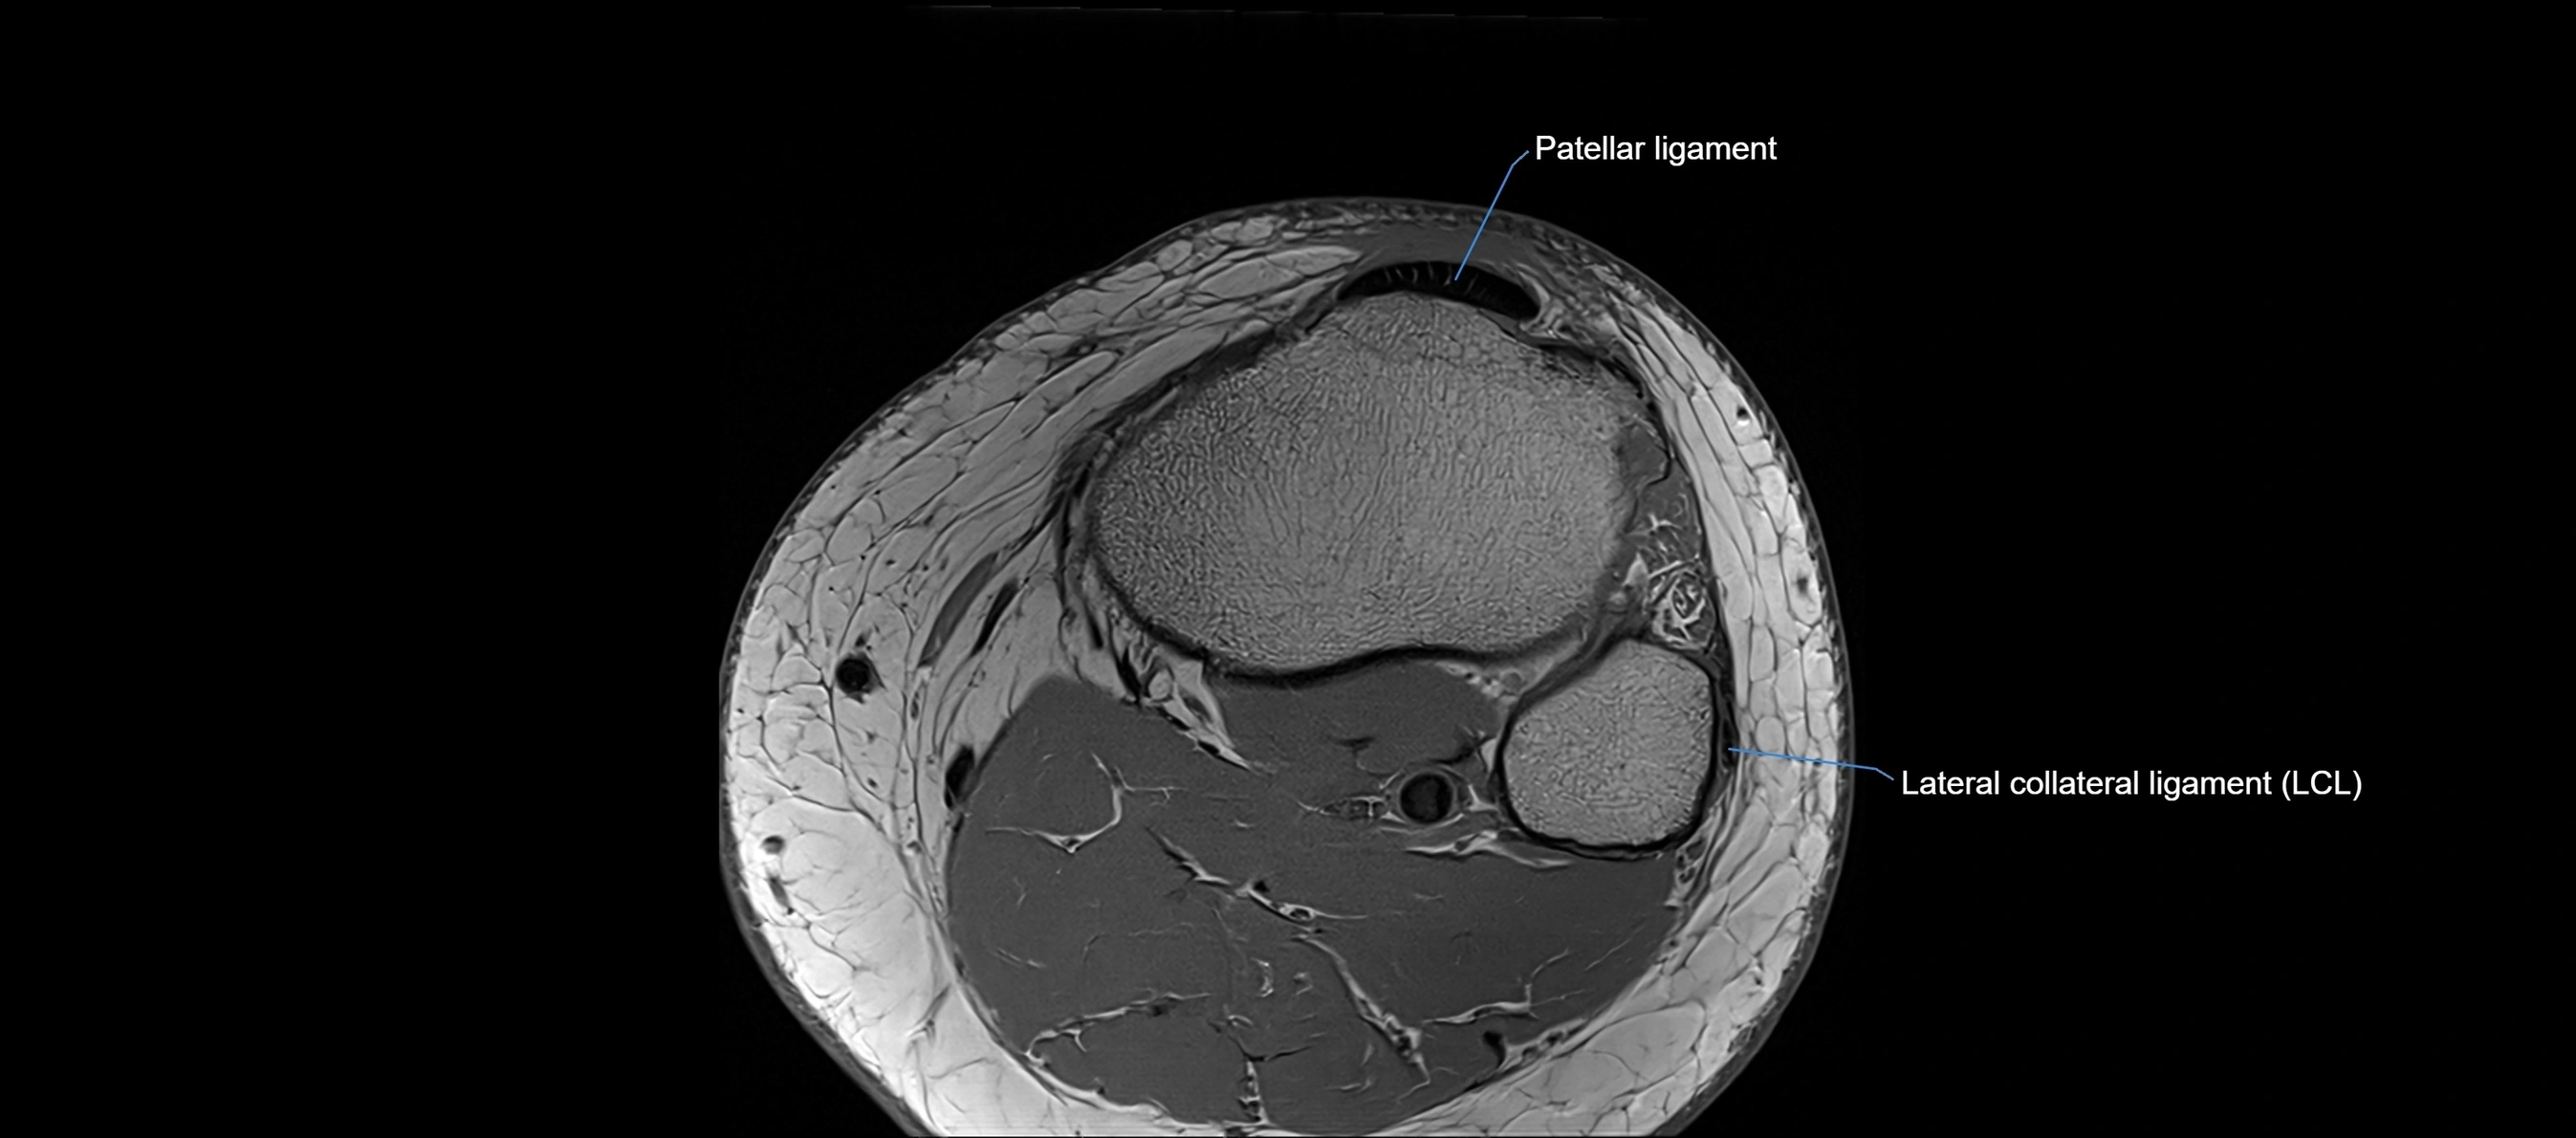

MRI images

image